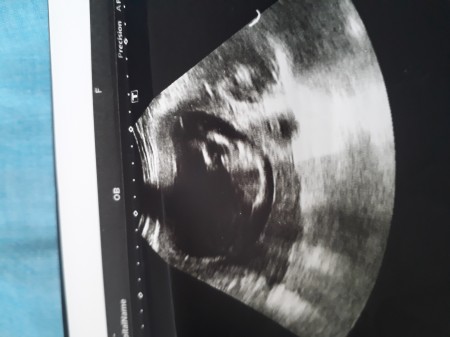

hanımlar doktor yüksek ihtimal erkek dedi bı cık>ntı goruyorum ben sizcede oyle mi ..degisme ihtilami var midir?

Gebelik haftası 12 haftalik